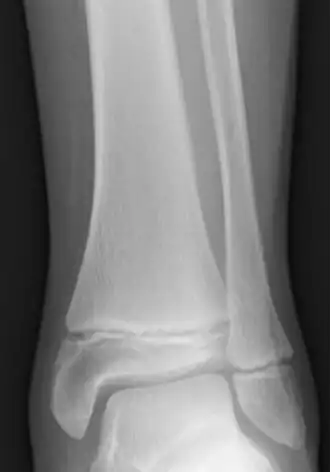

Les fractures de Salter-Harris sont des fractures impliquant les plaques épiphysaires et qui interférent avec la croissance, la taille ou les fonctions physiologiques[13].

3. Crowder et Austin, « Age ranges of epiphyseal fusion in the distal tibia and fibula of contemporary males and females », Journal of Forensic Sciences, vol. 50, no 5, , p. 1001–7 (PMID 16225203, DOI 10.1520/JFS2004542) :

« complete fusion in females occurs as early as 12 years in the distal tibia and fibula. All females demonstrated complete fusion by 18 years with no significant differences between ancestral groups. Complete fusion in males occurs as early as 14 years in both epiphyses. All males demonstrated complete fusion by 19 years »